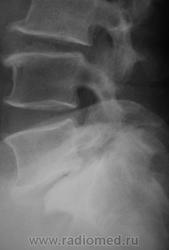

Спондилолистез L5-S1 - истинный, поэтому природа сама набедокуривши, сама и оберегает. Трудно представить безсимптомное течение, если бы это было последствием травмы. Очень рад, что Андрей Юрьевич приводит выдержки из Рейнберга. Судя по желтизне страниц - это первое издание.

По данному случаю:на мой взгляд, он является примером того, что попытки обяснить клинику(страдания пациента) только изменениями на R-граммах несостоятельны (если бы, у пациентки были жалобы,скажем на боли в области поясницы, сделали бы вывод-"что вы хотите?!-деформирующий спондилёз, да ещё спондилолистез- из-за этого и болит"). Думаю, многие сталкивались такими направлениями: "Направляеться на R-графию пояснично-крестцового отдела позвоночника.D.S.:Исключить остеохондроз ".

Спондилолистез L5-S1 - истинный, поэтому природа сама набедокуривши, сама и оберегает. Трудно представить безсимптомное течение, если бы это было последствием травмы. Очень рад, что Андрей Юрьевич приводит выдержки из Рейнберга. Судя по желтизне страниц - это первое издание